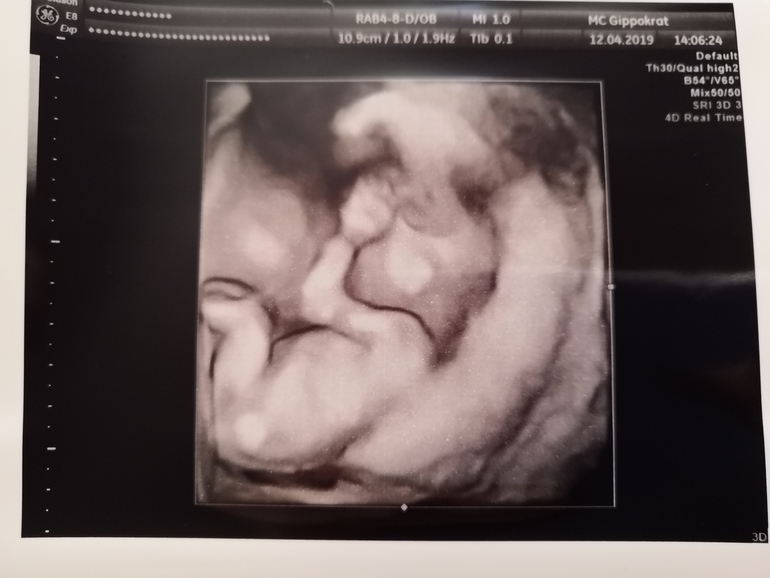

Первый скрининг делала в бесплатной ЖК, поэтому очень ждала 16-17 недели, сходить платно к своей любимой узистке. Сегодня 16,3 по месячным, радостная поскакала в клинику записываться, а мне - "она не делает на таком сроке УЗИ, только если на второй скрининг запишетесь к 20 неделе. Зачем вам на таком сроке УЗИ?" Блинский, расстроилась вся, настраивалась на хорошее, подробное узи... Девушка в регистратуре увидела мою расстроенную моську, спросила вас что-то беспокоит? Пришлось слукавить, сказала да... В итоге предложили короткую фетометрию, всего за 500 руб и прямо сегодня... Согласилась. Ну хоть что-то, элементарно сердцебиение послушать... Иначе мне параноику не дожить до 2го скрининга...

Посмотрели мою бусинку, растёт моя крохотулечка!🥰 131 грамм🤗Сердечко бьётся ❤️159 ударов! Ручками личико закрыла))) предположили пол, сказали "Очень похожа не девочку" 😁 эх, а я так хотела сыночка, имя уже придумала. А муж мечтает о доченьке, он думаю будет рад. Ему пол ещё не сказала. Целый день хожу и думаю, мама доченьки, уф это же такая ответственность!!! Я совершенно не готова к этому😁 постоянно мысленно представляла сына))) будем привыкать, лишь бы бусинка моя была здоровенькой! Всё, теперь на неделечку я спокойна... Дальше буду трястись и ждать 2ой скрининг... Узистка вслед сказала, чтоб раньше 20ой не припёрлась 😁 и шевелюшек мне раньше 20ой не стоит ждать, т.к по передней стенке... Вот такие делишки...